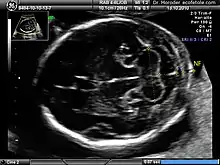

Enlarged NT and absent nasal bone in a fetus at 11 weeks with Down syndrome

Overall, the most common chromosomal disorder is Down syndrome (trisomy 21). The likelihood rises with maternal age from 1 in 1400 pregnancies below age 25, to 1 in 350 at age 35, to 1 in 200 at age 40.[4]